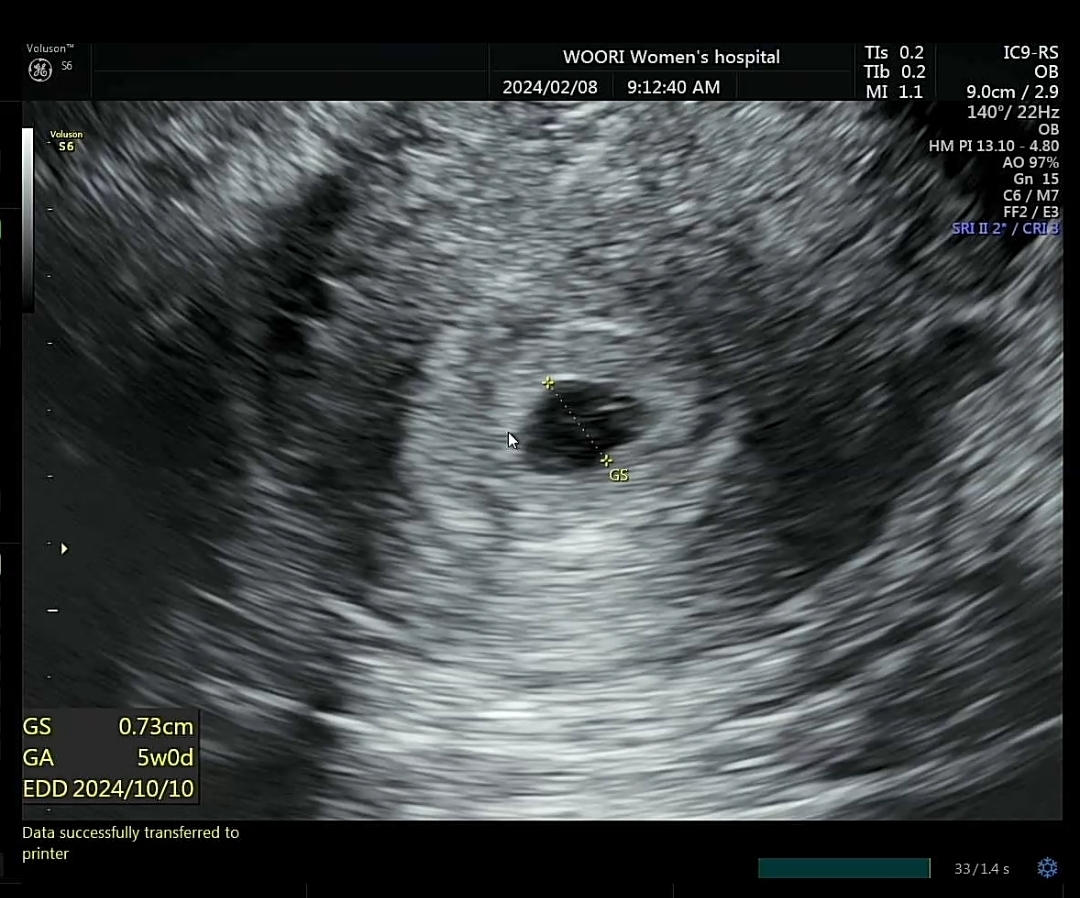

1/4 막생(생리주기 29일) 1/29 얼리테스트 두줄 확인 설명절 전에 아기집 보고 싶어서 병원 다녀왔는데 난황도 있고 자리 잘 잡았다고 하시네요👏 막생기준으로 5주0일인데 아기집 사이즈도 동그랗고 주수에 딱 맞는다는 이야기 듣고 왔어용! 작년 10월경에 유산하고 걱정했었는데 다시 잘 찾아와줘서 너무 고맙네요.